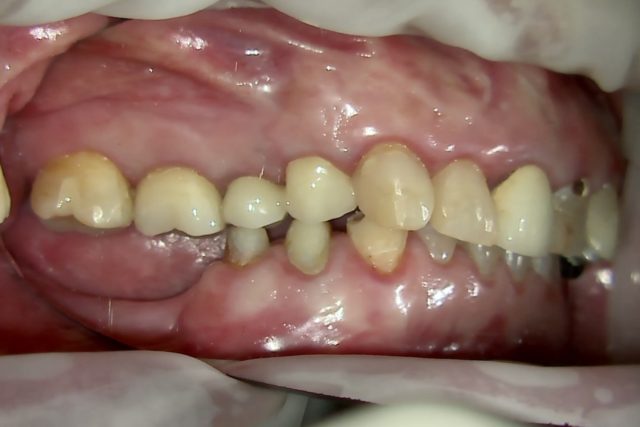

BEFORE